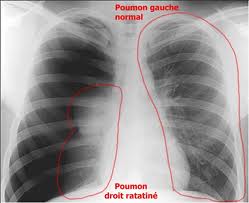

KOLDA : Le service de radiologie de l’hôpital régional redevient fonctionnel

Bonne nouvelle pour les populations de Kolda. La radio du centre hospitalier régional, à l’arrêt depuis quelques temps à cause de la destruction de son tube à rayon X, a repris service. Annonce faite par le directeur de l’hôpital Amadou Fall. A l’en croire, la machine a retrouvé une bonne santé avec « des images claires…